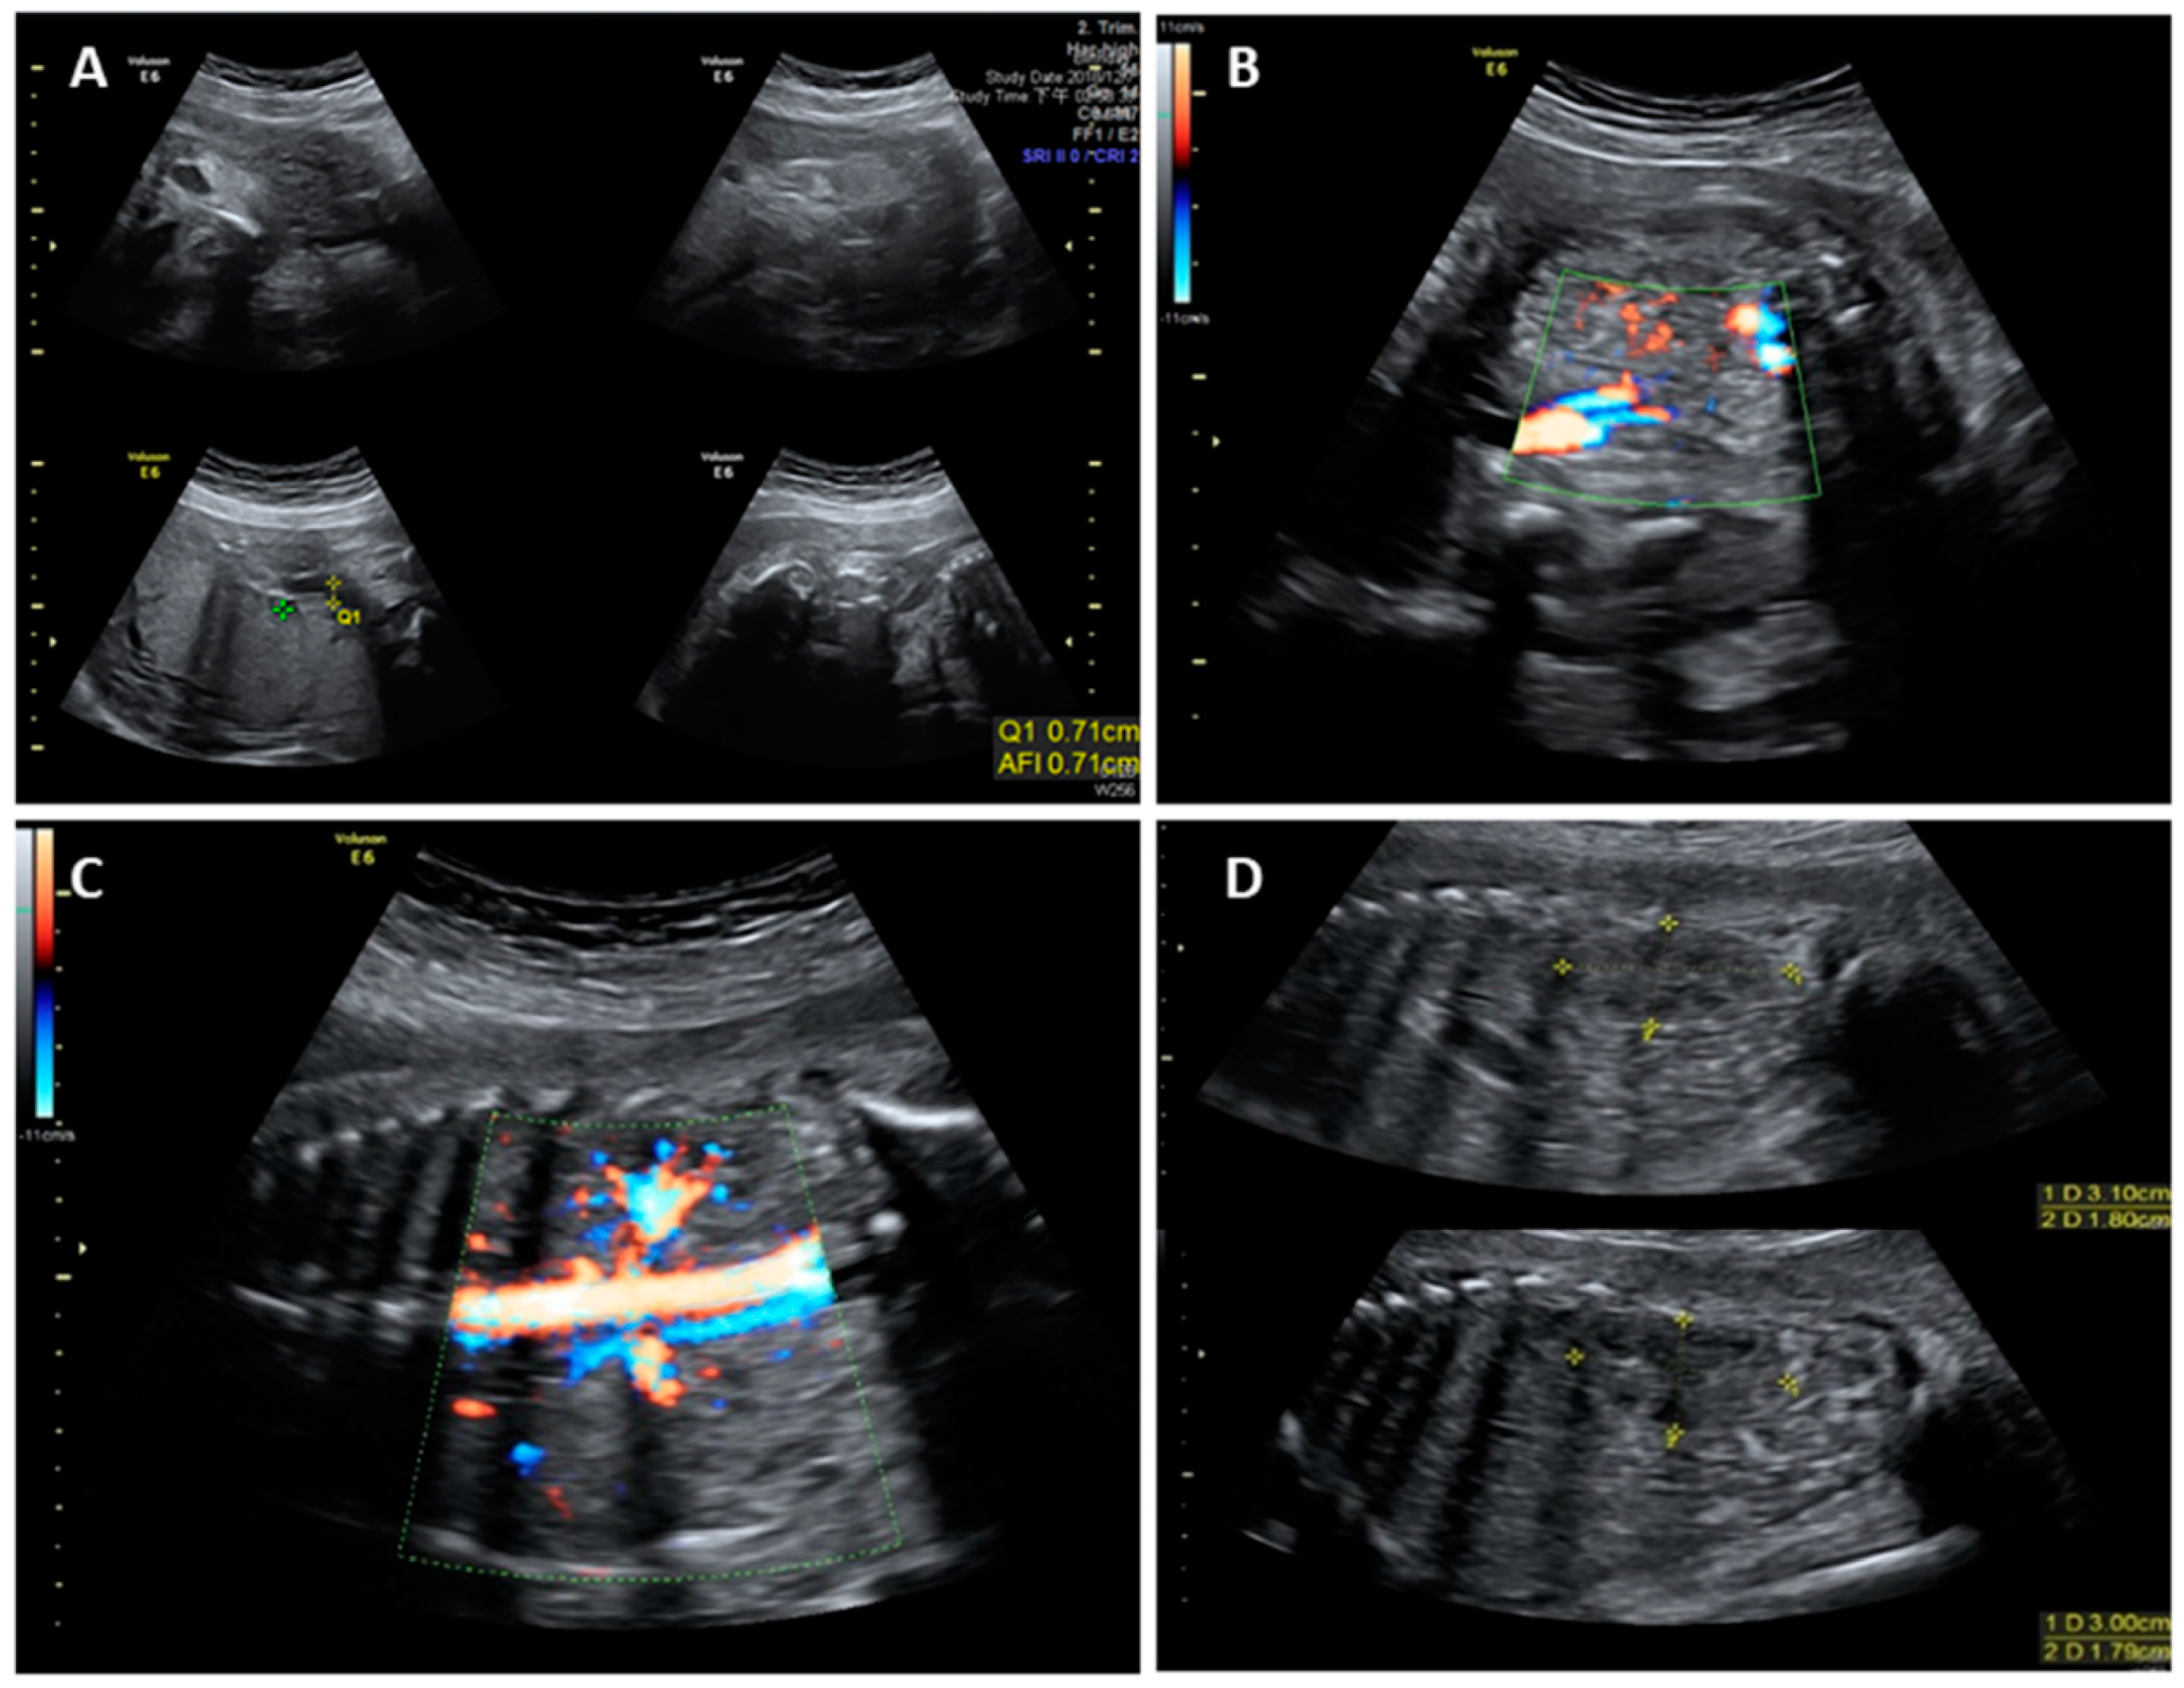

2. Case Report